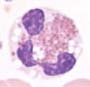

Die eosinophilen Granulozyten im Blut sind meist deutlich erhöht. Per Definition betragen sie mindestens 1.5 x109/L. Die Zellen sind meist zytologisch unauffällig. Blasten können vorkommen, betragen aber <20%.

Die eosinophilen Granulozyten und eosinophilen Vorstufen sind vermehrt und zeigen meist keine morphologischen Auffälligkeiten. Blasten können vorkommen und betragen <20%.